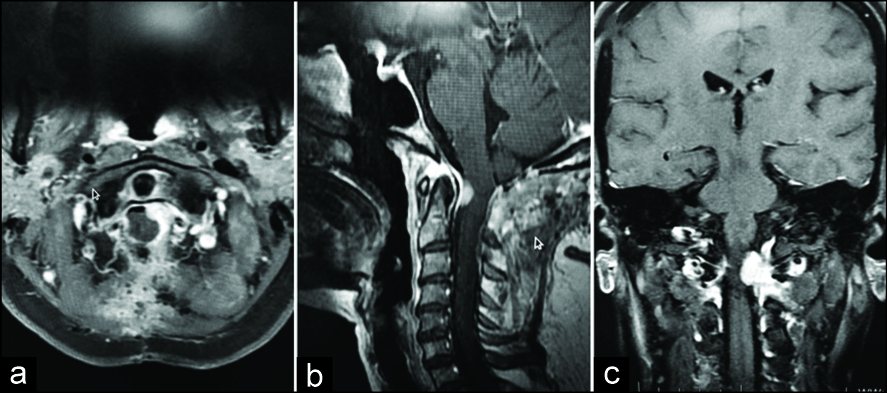

图2:

术后对比增强磁共振成像(a)轴向,(b)矢状,(c)冠状位图像显示右侧脑膜瘤完全切除,左侧残留肿瘤。